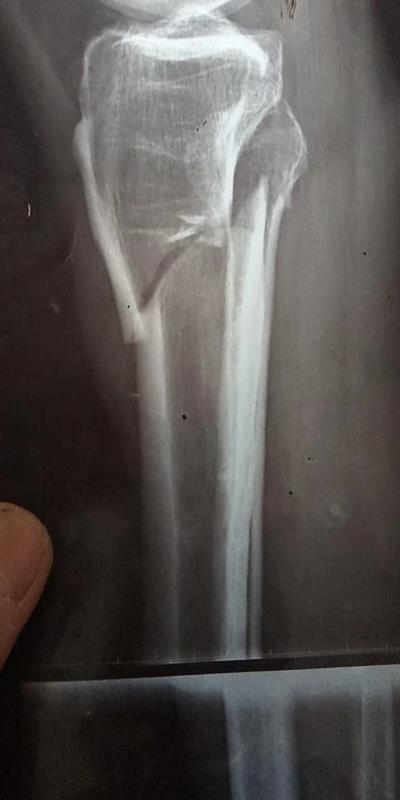

胫腓骨双骨折的,找我治疗两个月在家走路不拄拐杖三个半彻底的治愈。尿血患者经过七八家医院治疗,还到遵义医学院治疗过,共治疗一个多月没有效果的!!最后找我一周治愈。另一个在深圳打工痛的厉害不能上班去检查左肾0.5右肾0.6公分